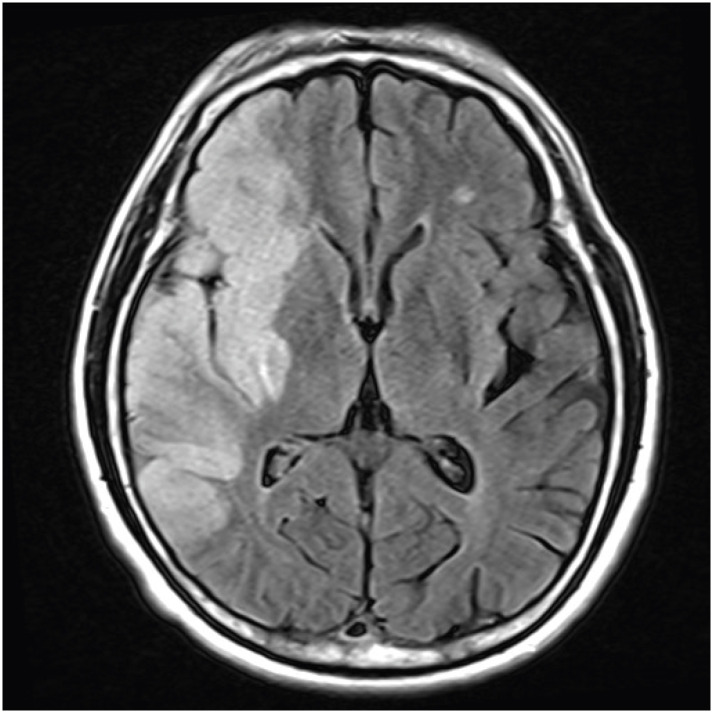

Crossed aphasia (CA) is a type of aphasia caused by cerebral hemispheric lesions on the same side of the dominant hand. The prevalence of CA is extremely rare. To the best of our knowledge, this is the first case report in Korea to conduct 6 years of long-term speech therapy in a case of a patient with CA. The patient was a 57-year-old right-handed man with aphasia caused by extensive acute infarction in the right middle cerebral artery territory. He presented with global aphasia, right-left disorientation, and agraphia. Language function recovered in the first 6 months and then plateaued.